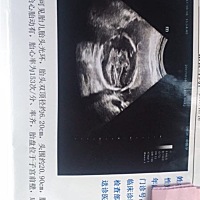

大神,五个多月了,帮看看男女

大家看看男孩女孩?